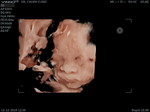

คลอด37วีคพอดี

คลอดแล้วจร้าาา???29มกราคม2563 เวลา16.39น.น้ำหนัก2,320gแข็งแรงดีค่ะ?แม่รกเกาะต่ำน้ำคร่ำน้อยเลยผ่าคลอดด่วนค่ะ